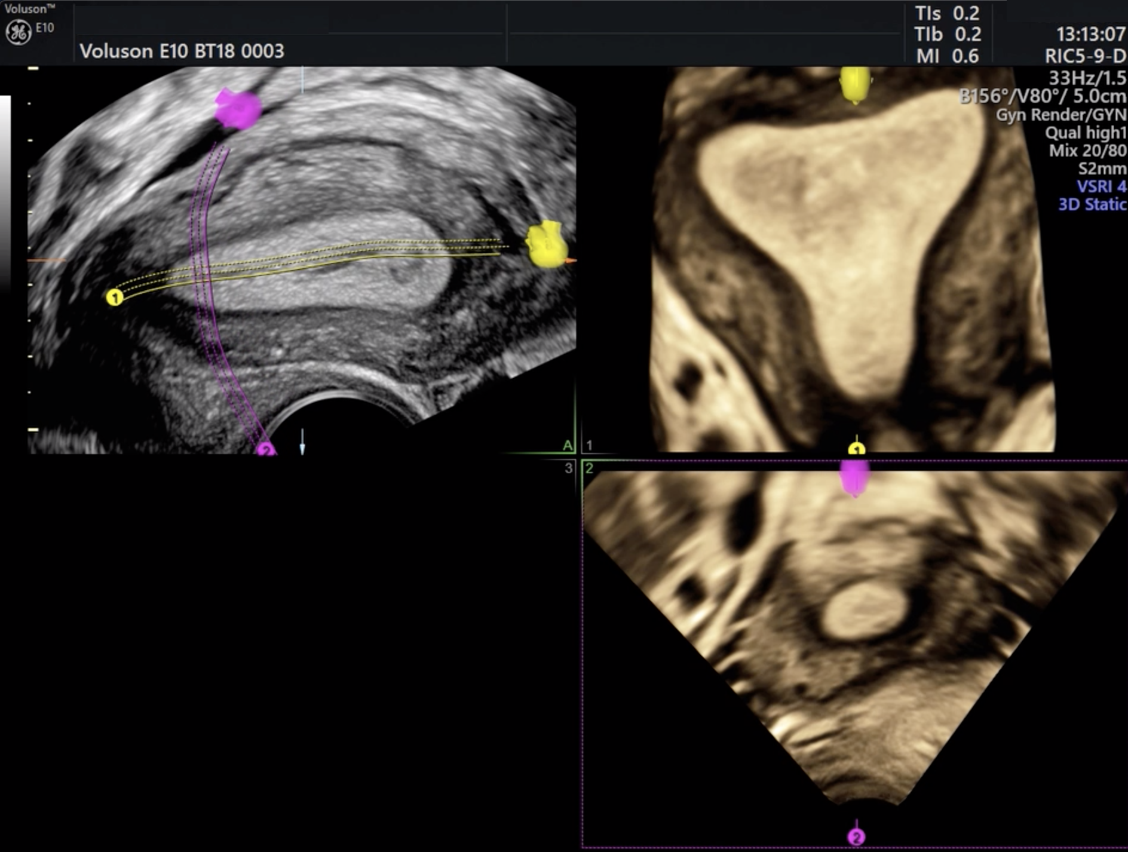

Imagem de ultrassom 3D mostrando nódulo de mioma uterino entre as setas